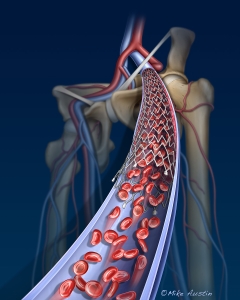

Internal Art Medical Illustration

Blending Art, Anatomy and Science for Creative Visuals

Patient & Professional Marketing

Welcome to my Patient and Professional Marketing page, where I harness the power of anatomical illustrations to educate and empower both patients and medical professionals. My unique approach combines artistry and education to convey complex surgical procedures and the utilization of medical devices in an easily understandable manner.